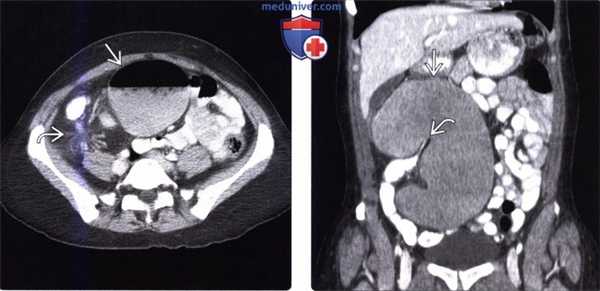

(Слева) На аксиальной КТ с контрастным усилением у мужчины 47 лет с жалобами на запор и отсутствие отхождения газов, у которого в течение шести дней сохранялось вздутие живота и боль, определяется заворот сигмовидной кишки в нижних отделах живота слева, при этом нисходящая петля перекрученной сигмовидной кишки имеет вид «клюва».

(Справа) На корональной КТ с контрастом у этого же пациента определяется характерное скручивание брыжейки на стороне заворота сигмовидной кишки.